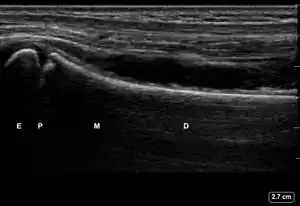

| 1 | Angulation of the distal bone segment[14] | ![]() Ultrasound view of angulation of distal bone segment (shown by arrow). E = epiphysis; P = physis; M = metaphysis; D = diaphysis. | |